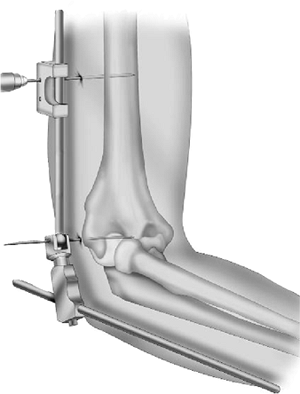

Distraction.

The ulna is separated from the humerus by turning the distraction screw

using a Hoffmann II Compact wrench. Most commonly, 2- to 3-mm

distraction is sufficient to accomplish the goals of the procedure (Fig. 8-13). Skin closure is usually deferred until the distraction is applied.

Figure 8-13.

Using the hand wrench the distraction device is advanced 2 to 3 mm or until the flexion arc occurs without evidence of articular contact. |